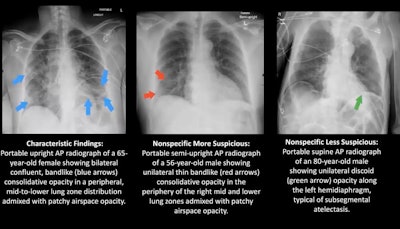

Two board-certified radiologists who were blinded to the RT-PCR results assessed each of the 60 chest x-rays in consensus and classified the images into one of three patterns: characteristic for COVID-19, nonspecific for COVID-19, and negative. The nonspecific patterns were further broken down into "more suspicious" or "less suspicious" for COVID-19, Igi explained.

What are characteristic findings on chest x-ray that are telltale signs of COVID-19? They can include the presence of bilateral patchy or confluent bandlike ground-glass opacity, or consolidation in a peripheral or middle to lower lung zone.

On the other hand, abnormal findings that are less suspicious for COVID-19 can include pulmonary edema, atelectasis, and interstitial changes.